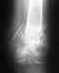

Давайте начнем с более подробного описания проблемы и рентгенограмм.